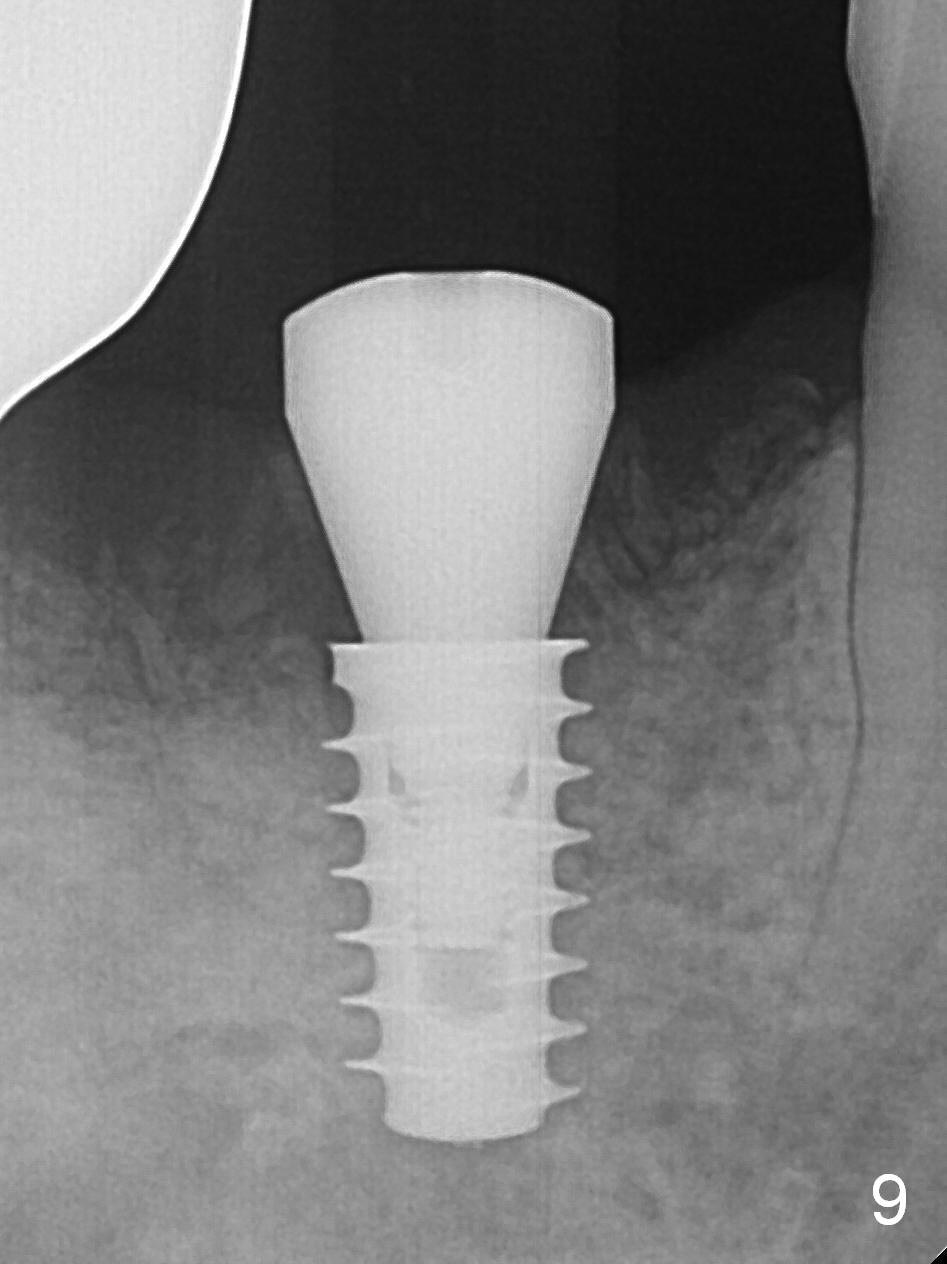

Extraction shows the large distal socket (Fig.1 D) and the thin and low septum (*) of the tooth #30. After Magic Split test confirms hard bone, osteotomy is initiated with 1.6 mm pilot drill with 11 mm stopper (Fig.2); there is 2.7 mm distance to the Inferior Alveolar Canal. Following Marking Bur, a 4.8 mm Magic Drill is used to finish the osteotomy with difficulty because of hard bone and ineffective local anesthesia due to infection. A 5x9 mm "dummy" implant is placed to determine the placement level relative to the distal crest (Fig.3 *). After removal of the dummy implant, an authentic one with the same dimension is placed with packing abundant allograft (.5-1.5 mm) and Osteogen (Fig.4 *); it appears that 4 to 5 threads (fins) of the implant (arrowheads) are engaged to the native bone for primary stability (>40 Ncm). Later more bone graft is placed distally (Fig.5 arrow). With the short implant placed not so deep, there is 6-7 mm clearance from the underlying canal (Fig.6). The patient is doing well 7 days postop (Fig.7). He feels that the provisional is too bulky buccally for the first 2 days postop. The buccal margin will be trimmed in another 2 weeks (dashed line). The patient in fact masticates on the right side postop. By the time he returns for provisional revision 1 months 10 days postop, he has mild pain. There is food entrapment. The provisional and the abutment are slightly loose, whereas the implant is stable with healing socket (Fig.8). A healing abutment is placed. The implant appears unstable nearly 5.5 months postop. The gap between the bone and implant seems to be large (Fig.9). The implant should have been larger and longer for fast healing. A healing screw is used instead. The site heals 10 months postop with an increase in bone density around the implant (Fig.10.) Prior to cementation of the final crown, the abutment is minimally exposed (Fig.11 (6.5x5.7(3) mm)). In fact the abutment screw becomes loose 2 months post cementation (1 year postop); it appears that crown/implant ratio is unfavorable (Fig.12). The implant is slightly placed mesially (cantilever). The patient cannot chew on the left. The tooth #19 is periodontally affected and the tooth #18 is missing. When bone loss is severe, the implant should be as large as possible and preferably tissue-level. The abutment screw is re-loosening 1.5 years post cementation (4 months post #19 socket preservation, Fig.13). The crown/implant ratio at #31 is more favorable than that at #30 (compare black lines). The crown at #31 has large contact area with the tissue-level implant (external), whereas the contact between the abutment and the bone-level implant is much less (internal). To prevent the abutment screw re-loosening (turning) in function, a screw driver (Fig.14 D) will be buried inside the crown/abutment after the screw is retightened. Make sure that the driver is in the middle of the access hole. Section the driver in situ obliquely (Fig.15); flat sectioning allows the driver to turn with the abutment screw in function. After insertion of plumber tape around the sectioned screw driver, use composite to fix the driver in place and seal the access hole (Fig.16). Occlusal check suggests weak link between the abutment and bone-level implant at #30.